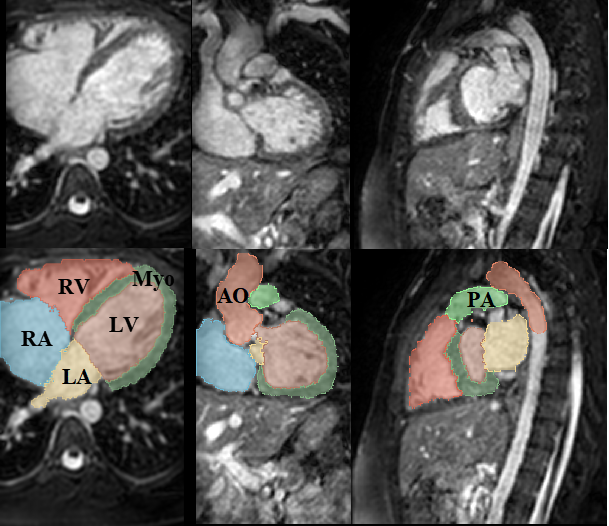

Figure 1: Examples of cardiac images and WHS results: (a) displays the three orthogonal views of a cardiac CT image and its corresponding WHS result, (b) shows example cardiac MRI data and the WHS result. LV: left ventricle; RV: right ventricle; LA: left atrium; RA: right atrium; Myo: myocardium of LV; AO: ascending aorta; PA: pulmonary artery.

In recent decades, significant advances in cardiovascular disease (CVD) research and practice have been made to improve the diagnosis and treatment of heart disease [1]. Cardiac image segmentation is an important first step in many applications. It partitions the image into several semantically (i.e., anatomically) meaningful regions, based on which quantitative measures can be extracted, such as the myocardial (Myo) mass, wall thickness, left ventricle (LV), right ventricle (RV) volume, left atrium (LA), right atrium (RA), ascending aorta (AO) or the whole aorta, and the pulmonary artery (PA)[23, 22], as Fig. 1 shows. Despite its wide range of applications, automated WHS remains challenging, e.g., systole and diastole of the heart, deformation of the heart’s shape from pathological and physiological changes, as well as differences in image acquisition equipment and motion artifacts that appear in the clinical data. State-of-the-art deep segmentation methods[12, 8, 16, 18, 10, 24, 5, 21] can automatically learn robust feature representations with satisfactory performance. However, standard deep neural networks cannot learn global structural constraints on semantic labeling, which is often crucial in the biomedical domain. For example, in WHS segmentation, we know in advance that Myo always encloses LV, and another global constraint is mutual exclusion for different labels.